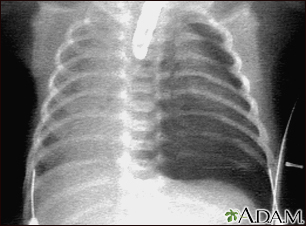

X-raysA chest x-ray is nearly always taken on a patient admitted to the hospital to confirm a pneumonia diagnosis.

A chest x-ray may reveal the following:

- Complications of pneumonia, including pleural effusions and abscesses

- White areas in the lung called infiltrates, which often indicate infection